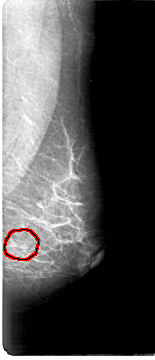

D_4155_1.RIGHT_MLO

FILE: D_4155_1.LEFT_MLO.OVERLAY

TOTAL_ABNORMALITIES 1

ABNORMALITY 1

LESION_TYPE CALCIFICATION TYPE PUNCTATE-FINE_LINEAR_BRANCHING DISTRIBUTION CLUSTERED

ASSESSMENT 0

SUBTLETY 2

PATHOLOGY MALIGNANT